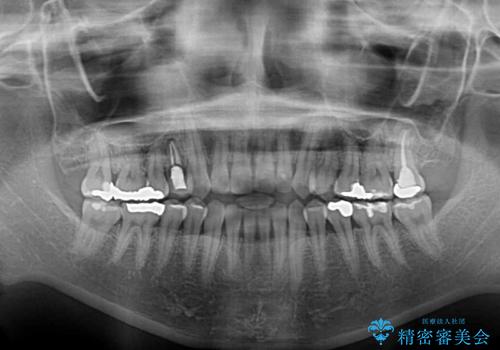

- 上下前歯が非接触となっている咬み合わせを気にして来院された患者様です。

開咬となっている原因の大半は、舌の突出癖によるものであるため、治療開始前から舌のトレーニングを開始し、スムーズに治療が進むようにしました。

- 症状により、抜歯が必要な場合があります